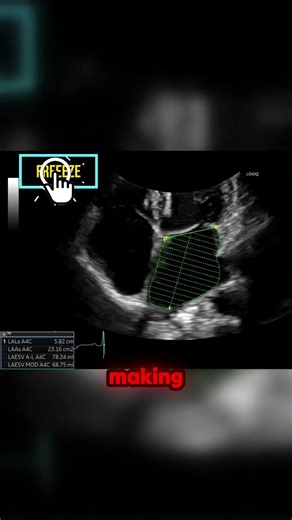

Complete 2D Transthoracic - How to Setup Echo